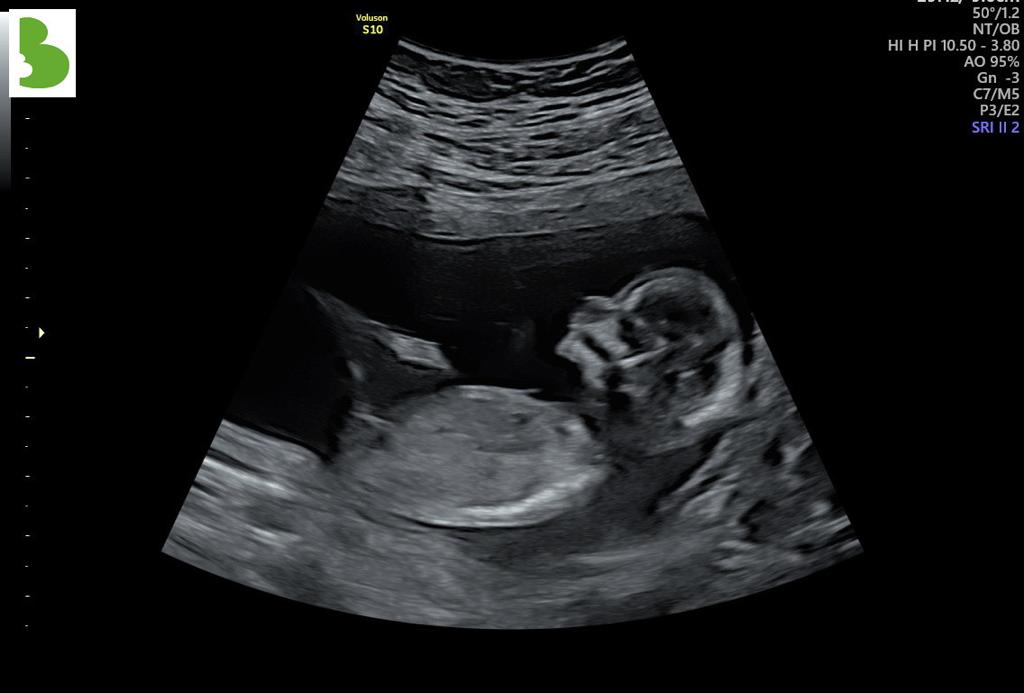

Då var det dags igen, vi väntar en liten till apa i januari. Vi bara längtar!

Nu och en tid tillbaka har jag känt sparkar som gör att det är ett svar på att man gör något gott! Man skapar något med sin egna kropp! Det är helt otroligt och vi är så spända på att få träffa den Lille i magen.